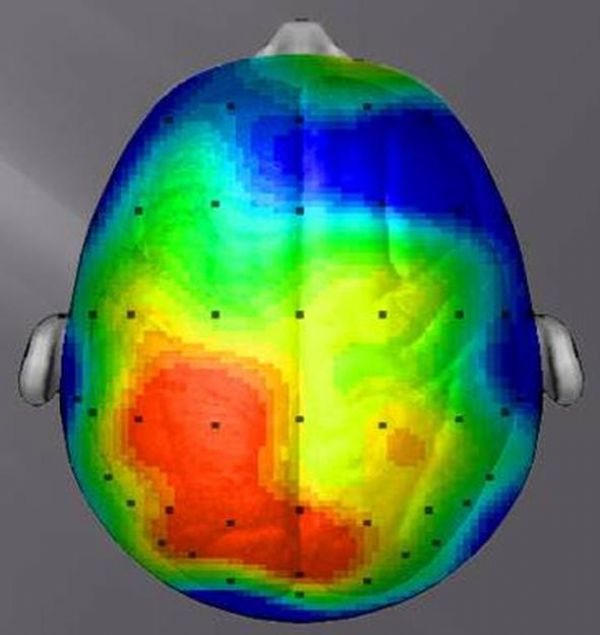

20 dakikalık yürüyüşün ardından ise böyle...